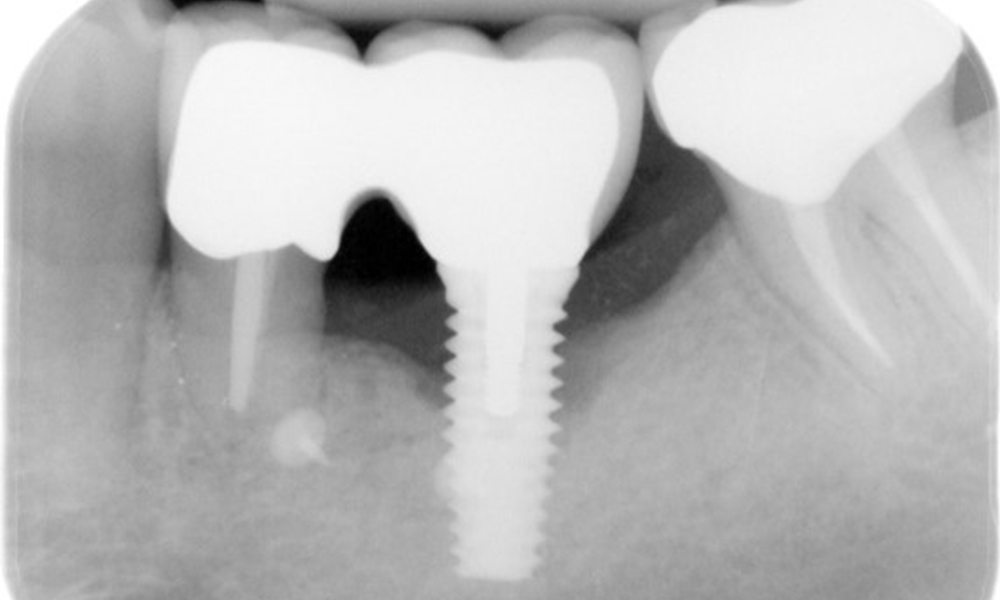

Röntgenaufnahme zeigt Verlauf des Knochenabbaus

Die Röntgenaufnahmen zeigen den Verlauf des Knochenabbaus im Bereich des Implantats Regio 36: ZF vom 11.02.2021 (links) und ZF vom 18.01.2024 (rechts)

OPG: 26.02.2024 ZF: 18.01.2024